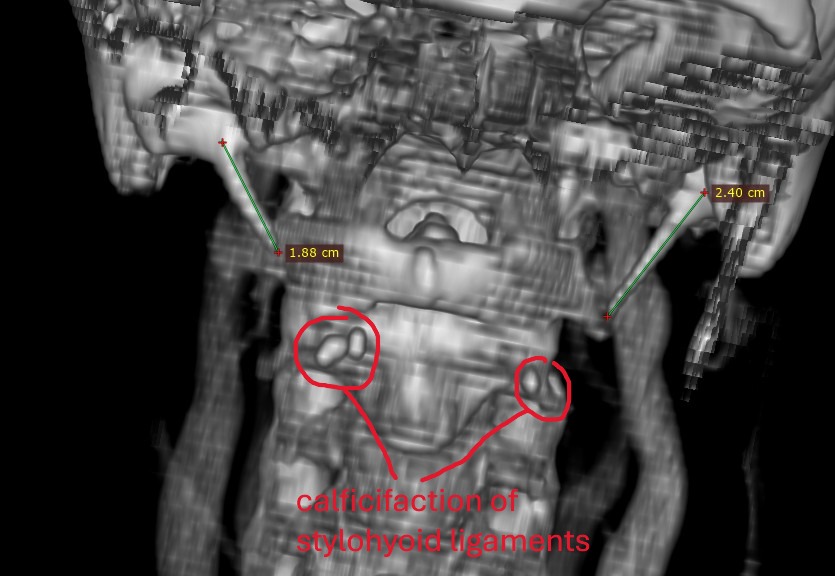

@chrEagle see attached annoted images (5 here of the axial view, and a 3D model in a following post)

Further down, there is a pocket of calcified stylohyoid ligament on both sides. It may not look like much, but these little calcification pockets can irritated nerves.

@chrEagle I don’t have the number, and it may be hard to see in 3D. Most radiologists use the axial view (the view I posted) when assessing for compression anyway, so it may be better to just show your doctor image #3 and explain to them that you think your left ICA is compressing your left IJV (and against your posterior digastric). A surgeon can move the ICA which may be all you need IJV-wise. However, you do have those small pockets of calcified stylohyoid ligaments and I wonder if they are contributing to any symptoms. Doesn’t appear they are contributing to anything vascular-wise at least.